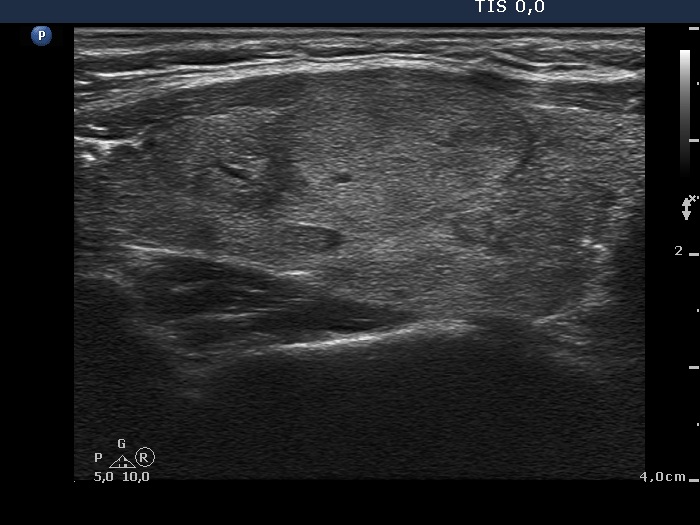

Ultrasonography. The thyroid was echonormal. There were multiple moderately hypoechogenic lesions in the right lobe. The palpable nodule was echonormal and presented halo sign and perinodular blood flow.

Taking the ultrasound presentation into account, the risk of oxyphilic tumor was even lower because the ultrasound pattern corresponds either to hyperplastic nodules or to an autoimmune thyroiditis.